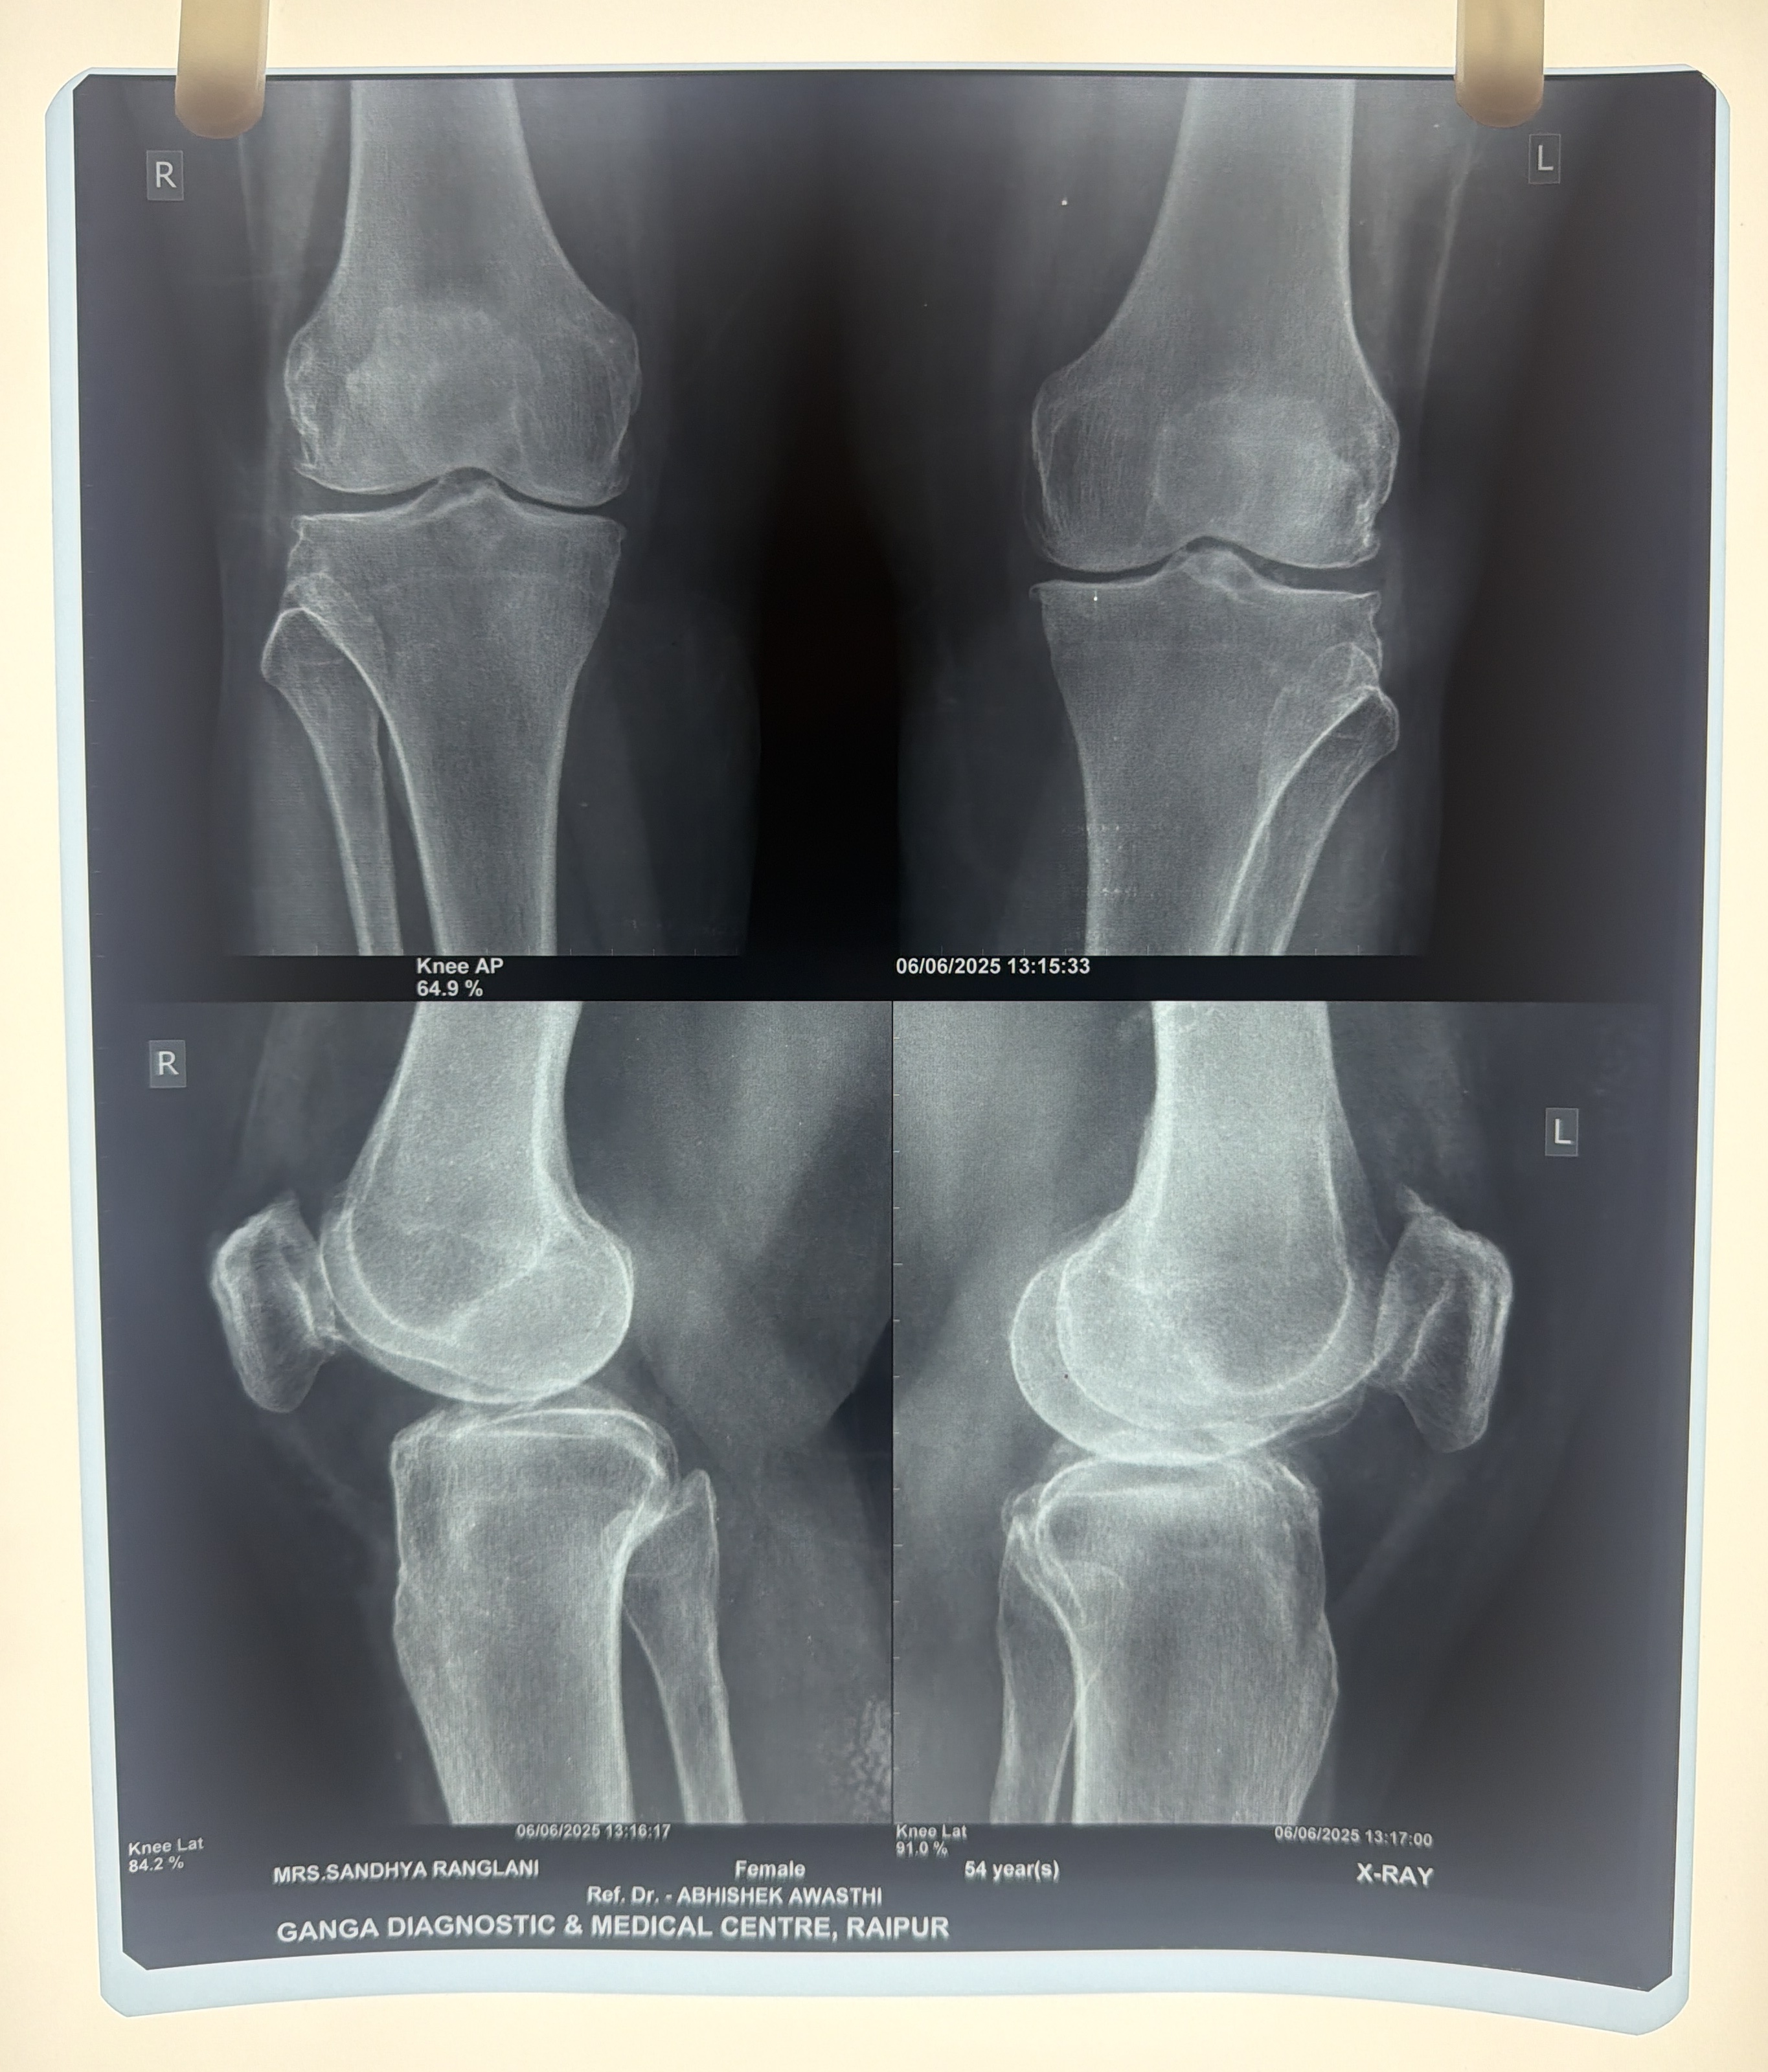

Sandhya Ranglani (Khairagarh-CG)

Before Before After After

Osteoarthritis Knee